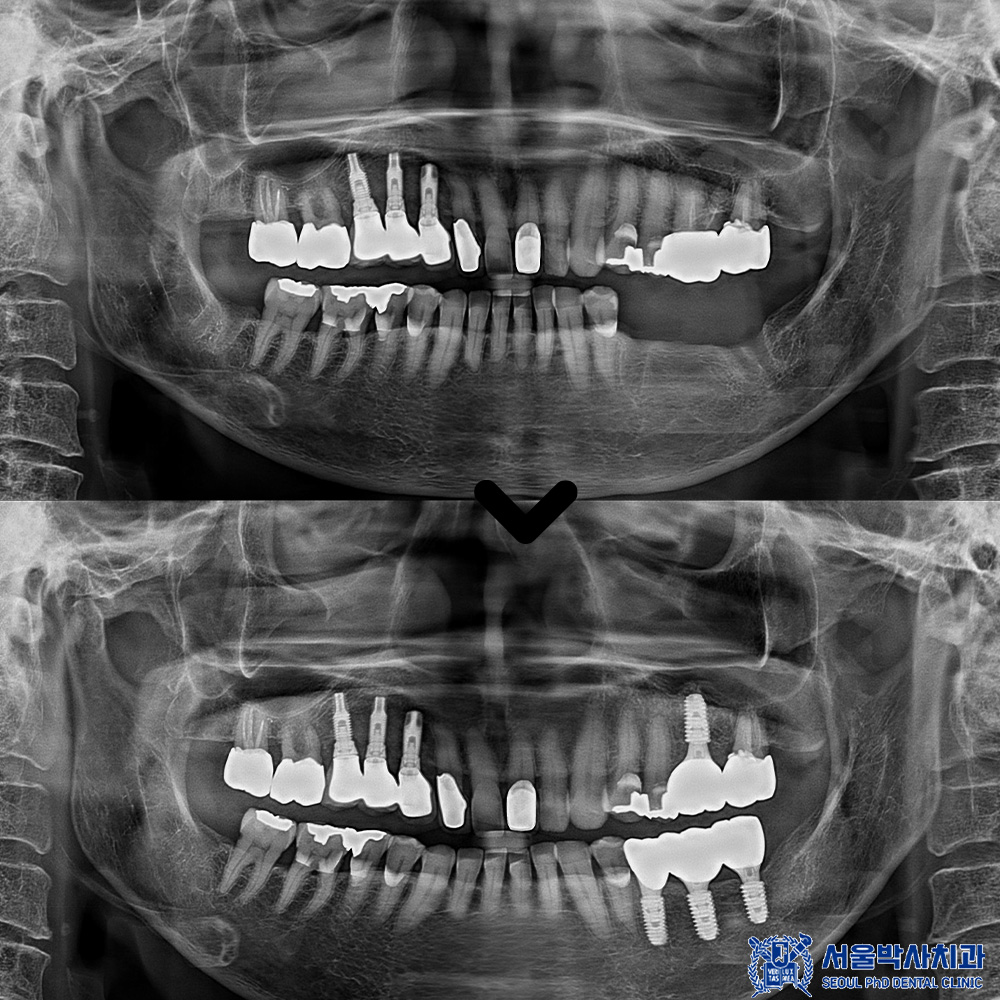

치유기간을 기다린 후

위쪽도 본원 원내기공소에서

직접 제작한 개인 맞춤형

임플란트 보철물을

세팅해 드렸습니다.

마무리 후 사진입니다.

환자분께 골다공중 주사제 체크를 잘하여

안정적으로 임플란트 수술을

할 수 있게 도와드렸고

무절개임플란트 후

만족도가 매우 높으셨습니다.

역시 소개로 잘 왔다며

좋아해주셨답니다.^^